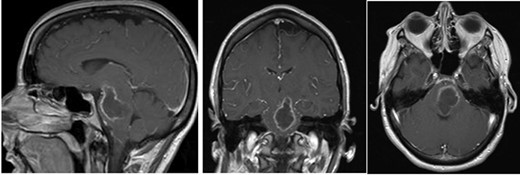

Post-op axial, coronal and sagittal T1 post-contrast MRIs demonstrating decrease size of rim enhancing pontine abscess.

Three days after initial presentation, she underwent sub-occipital craniotomy for microsurgical abscess drainage. Initial consideration was given to a stereotactic procedure; however, an open approach was ultimately chosen due to surgeon preference. Intraoperative neuro navigation was used with subsequent creation of a posterior fossa craniotomy. This approach was chosen over a retrosigmoid approach, given the midline nature of the lesion. The dura was opened over the right cerebral hemisphere and tonsil at which time pus was expressed and was cultured immediately at the operative site. We were unable to dissect the roof of the fourth ventricle secondary to a large volume of pus and instead retracted the bilateral tonsils and resected a small amount of the inferior vermis. Facial colliculus was localized and an incision was made in the midline medial raphae. Incision into the brainstem did not express any purulence, so the wound was copiously irrigated and subsequently closed without advancing further into the brainstem. Cultures from the abscess grew step intermedius and antibiotics were narrowed accordingly. Over the next several weeks, the patient remained afebrile with no leukocytosis, but there was concern for persistent infection due to lack of clinical improvement. Repeat MRI demonstrated enlargement of the residual abscess (Fig. 2a–c), and she was taken back to the operating room for repeat abscess drainage via the same sub-occipital craniotomy incision. During this procedure, the roof of the fourth ventricle was visualized and dissected through before localization of the vagal trigone. Midline raphae was once again opened and intraoperative MRI navigation confirmed the locations of the abscess. Microscopic dissection was performed in the midline between facial colliculi, and spinal needle was passed into the opening with subsequent aspiration of 9-ml purulent fluid, re-aspiration attempt and closure. Repeat gram stain and culture failed to reveal any organisms.